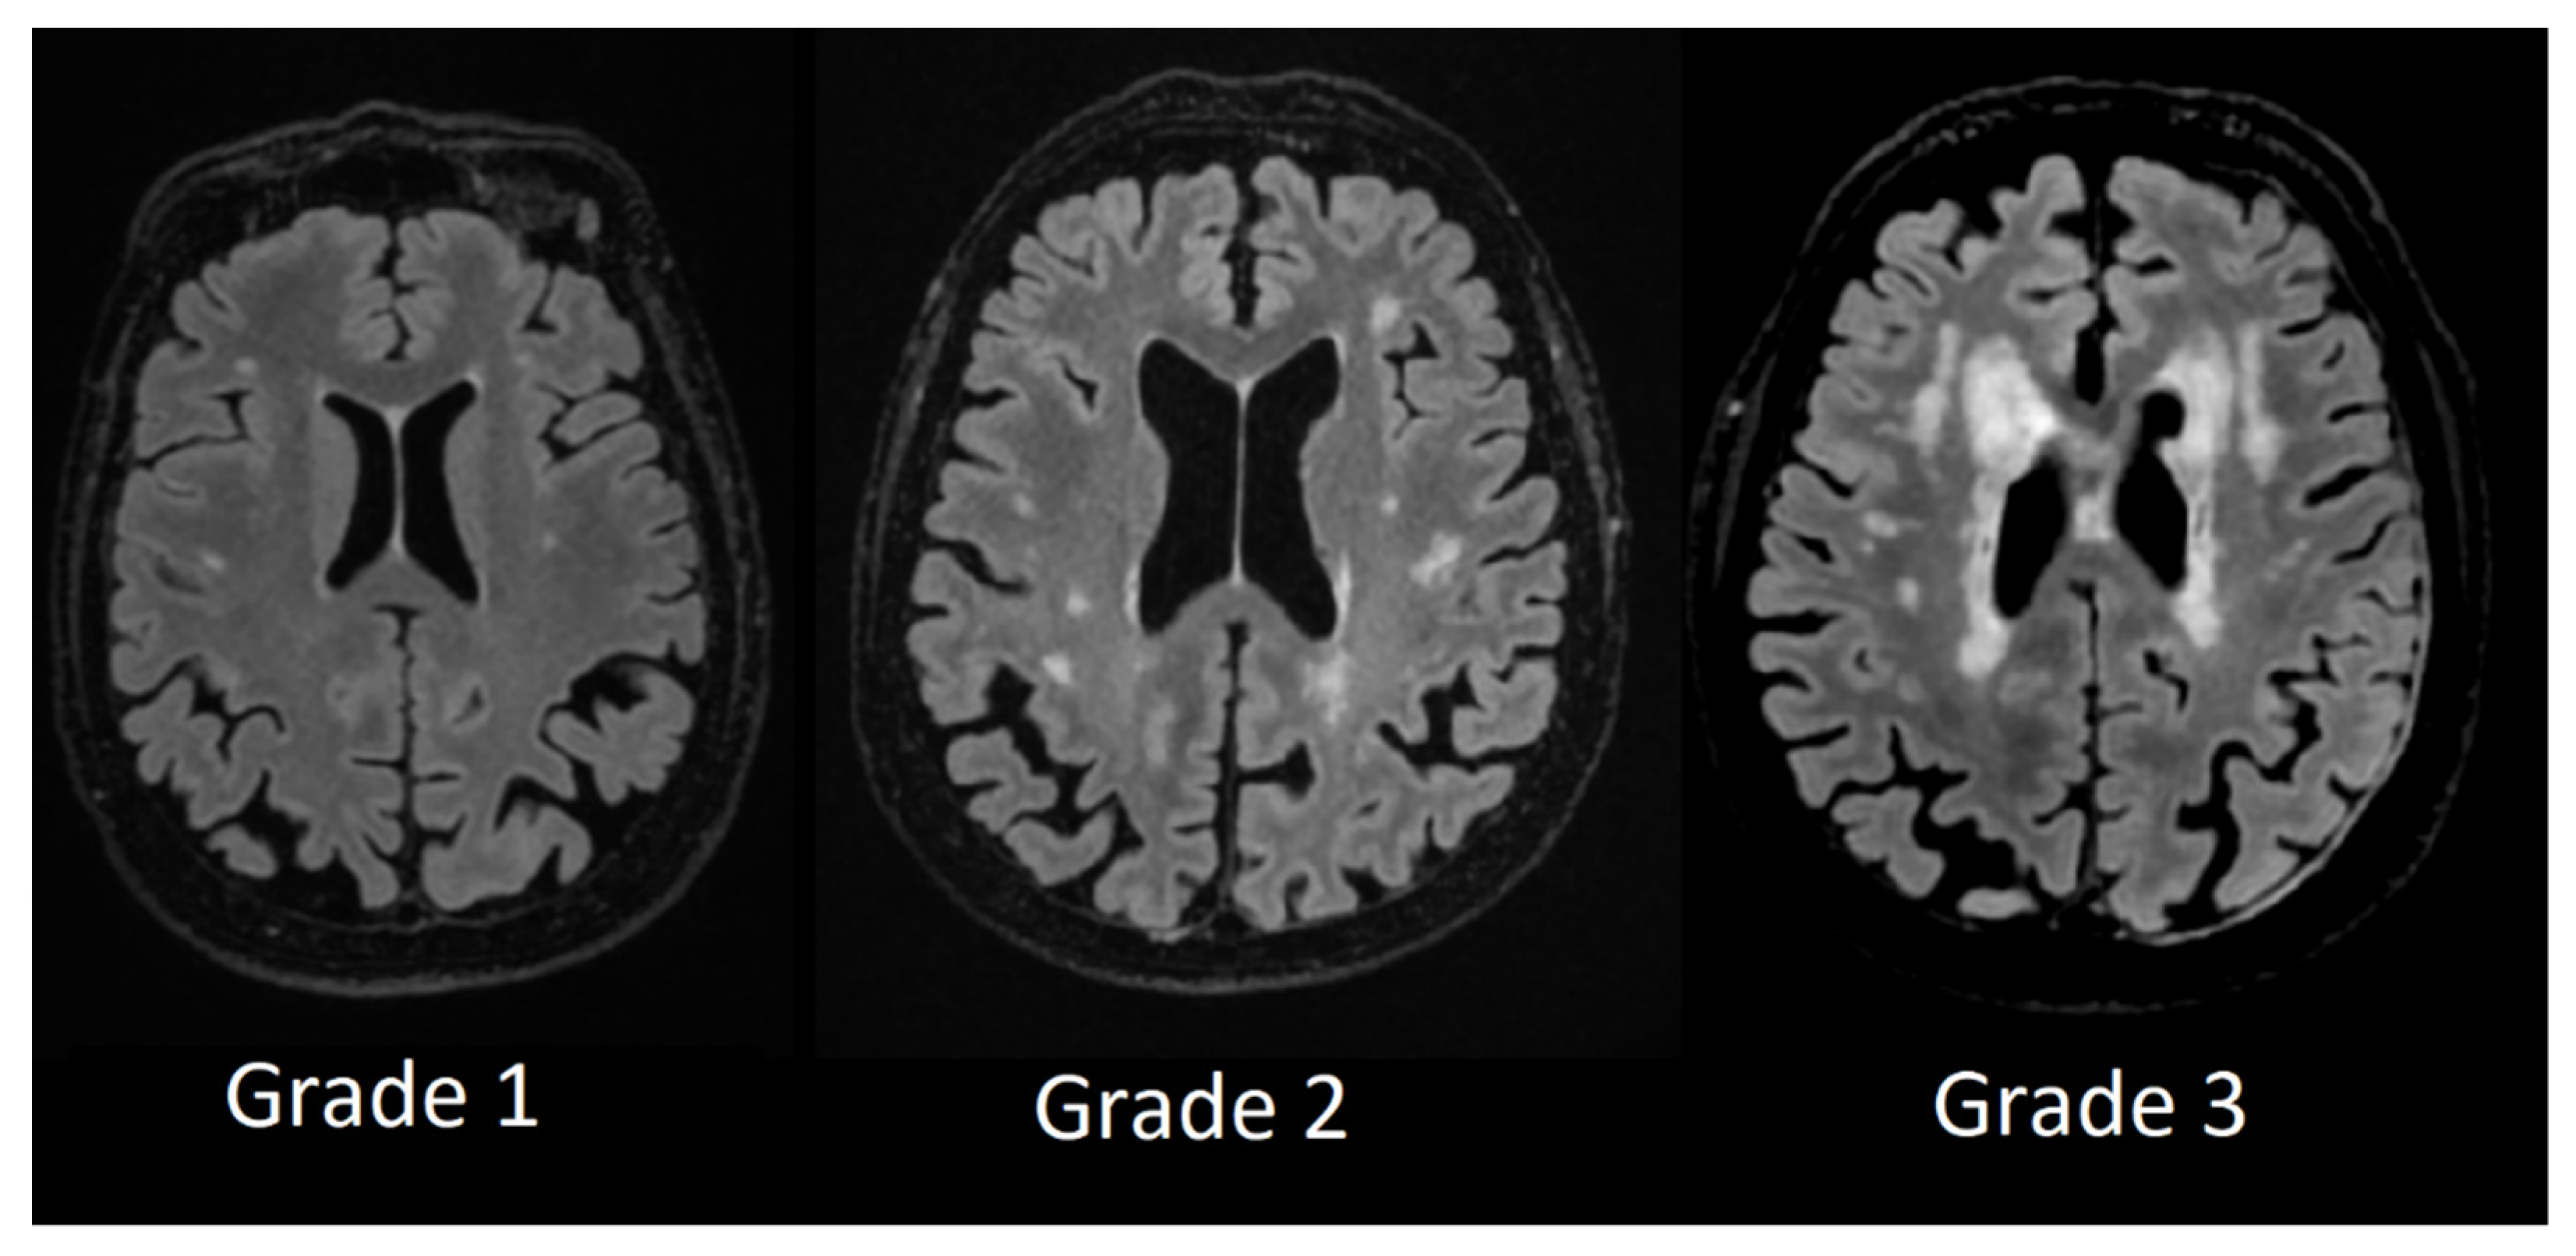

Perivascular space grading was partially based on Potter et al. [13] grading scale. We evaluated basal ganglia PVS (Type 1, see Figure 1) and centrum semiovale PVS (Type 2, see Figure 2) by the rating scale: grade 0–no PVS dilatation; Grade 1–1 to 10 dilatated PVS; Grade 2–11 to 20 dilatated PVS; Grade 3–21 to 40 dilatated PVS; Grade 4–>40 dilatated PVS.

In periventricular white matter lesions Grade 1 was assigned to patients with mild hyperintensities that occurred along with the ventricular horns, also referred to as ventricular caps, Grade 2 was assigned to patients with more extensive hyperintensities and Grade 3 was assigned to patients with lesions that were extending into deep white matter (see Figure 3).

Figure 3. Periventricular white matter hyperintensities based on Fazekas scale from Grade 1 to Grade 3.